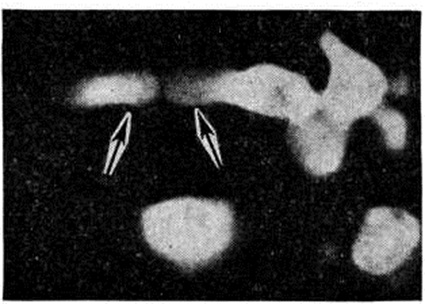

Кандидоз кожи проявляется в виде подострых дерматитов в складках кожи, изредка с образованием абсцессов и изъязвлением. При гистологический исследовании отмечается межклеточный отёк эпидермиса, паракератоз, акантоз и прорастание нитей грибка в некротизированный эпидермис (рисунок 2). Воспалительная инфильтрация преимущественно из сегментоядерных лейкоцитов наблюдается в основном в дерме. Иногда наблюдается формирование ограниченных абсцессов с наличием распадающихся сегментоядерных лейкоцитов. Впоследствии образуются гранулемы, состоящие из лимфоцитов, эпителиоидных и гигантских клеток (рисунок 3).

Рис. 3. | ||

Гистологический картина изменений в метастатических очагах различных органов и тканей не имеет строго выраженных специфических черт. В начальной стадии кандидозного процесса наблюдается некротически-экссудативная воспалительная реакция, чаще гнойного характера, реже с преобладанием в инфильтрате лимфоцитов. Интенсивность разрастания грибка зависит от жизнеспособности ткани: там, где некроз выражен резче, нитей грибка значительно больше. При хронический течении процесса вокруг некротически-экссудативного очага воспаления происходит разрастание соединительной ткани или наблюдается формирование гранулемы (смотри полный свод знаний), напоминающей таковую при туберкулёзе (рисунок 3). Ликвидация грибка в организме происходит в основном за счёт лизосомальных ферментов сегментоядерных лейкоцитов (рисунок 4), то есть в результате так называемый внеклеточного фагоцитоза, поэтому рост грибка в гнойном очаге обычно тормозится. Присутствие большого количества сегментоядерных лейкоцитов препятствует размножению грибка, лейкоциты как бы облепляют элементы грибка и, подвергаясь распаду, отграничивают его от окружающей ткани (рисунок 5). Как показывают электронно-микроскопические исследования, в клетках грибка нарушается целостность цитоплазматической мембраны и появляются аутофагические вакуоли в цитоплазме. Фагоцитоз грибков сегментоядерными лейкоцитами встречается редко и касается в основном нежизнеспособных клеток грибков; в цитоплазме же макрофагов (рисунок 6) и гигантских клеток грибок может находиться длительное время и быть жизнеспособным — так называемый эндоцитобиоз. Поскольку грибок способен к внутриклеточному паразитированию, то наличие его жизнеспособных форм свидетельствует о том, что воспалительный процесс имеет затяжной характер.